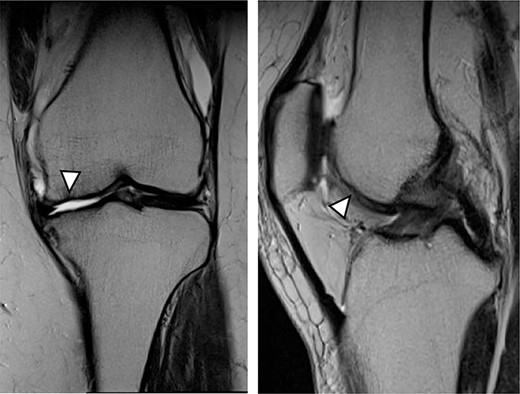

MRI showed cartilage injury of the medial femoral condyle (arrowhead).

As a control case, a 51-year-old female (BMI, 24.1 kg/m2) presented with 4.5 years of left knee medial joint pain. Preoperative Tegner scores, Lysholm scores and KOOS scores are shown in Table 1. Preoperative radiographs of the left knee joint showed mild medial osteoarthritis (OA) of the knee and hip–knee–ankle (HKA) angle of 1.3-degree varus. MRI showed cartilage injury at the MFC (Fig. 6). Approximately 0.5 g of the healthy cartilage was harvested from less weight-bearing regions of the intercondylar notch using arthroscopy. The specimen was sent to J-TEC for cartilage culture. At 4 weeks after the harvest, the microfracture was performed at a 4-mm power pick at the cartilage lesion, and the two-stage implantation of tissue-engineered cartilage-like tissue (JACC) was performed on the cartilage injury site (4.5 × 5.5 cm; Outerbridge classification, Grade III), and then the tissue implantation site was covered with periosteum taken from the tibia of the same patient (Fig. 7). Knee joints were immobilized for 4 weeks with a soft knee brace. A ROM exercise is started with a continuous passive motion device at 3 weeks after surgery. Partial weight-bearing (30% body weight) was allowed at 4 weeks, and full weight-bearing permission was given from 8 weeks after the surgery.

MRI findings at 1 year after the surgery indicated signal intensity area in the grafted area for the patient with JACC (Fig. 8), whereas the patient who underwent Reveille CP exhibited greater thickness at the grafted area as compared to the surrounding healthy cartilage (Fig. 9). The MOCART score at 1 year after the Reveille CP surgery (60 points) was higher than that of JACC (50 points).